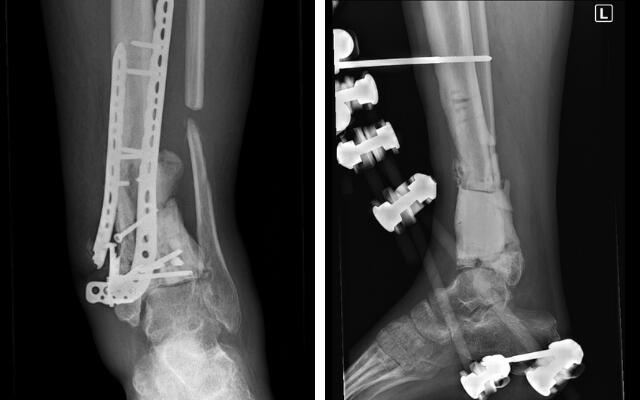

Podczas prac domowych uległem poważnemu wypadkowi, spadając z drabiny. Konsekwencje były tragiczne – doznałem otwartego złamania kości piszczelowej, strzałki oraz kostki. Przeszedłem długotrwałe leczenie: cztery operacje, dwa przeszczepy kości, zastosowano również terapię podciśnieniową VAC. Niestety, kości nadal się nie zrastają!